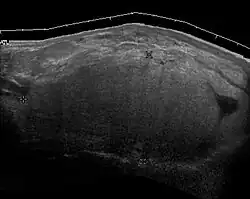

Medical imaging

Medical ultrasonography and magnetic resonance imaging (MRI) of liposarcomas are helpful and often essential in determining their extent, surgical accessibility, and relationship to any observed organ dysfunctions. Since ultrasonography is usually unable to distinguish a liposarcoma from a benign lipoma, MRI is the initial imaging of choice to provide evidence relative to making this distinction.[67]

-

Fig. 5 Ultrasonography of a liposarcoma with high-echo areas reflected from its lipomatous matrix and low-echo areas reflected from its non-lipomatous areas.[69] -

Fig. 6 Ultrasonography of a liposarcoma mimicking a lipoma. This homogeneous high-echoic mass has the same appearance as a lipoma.[69] -